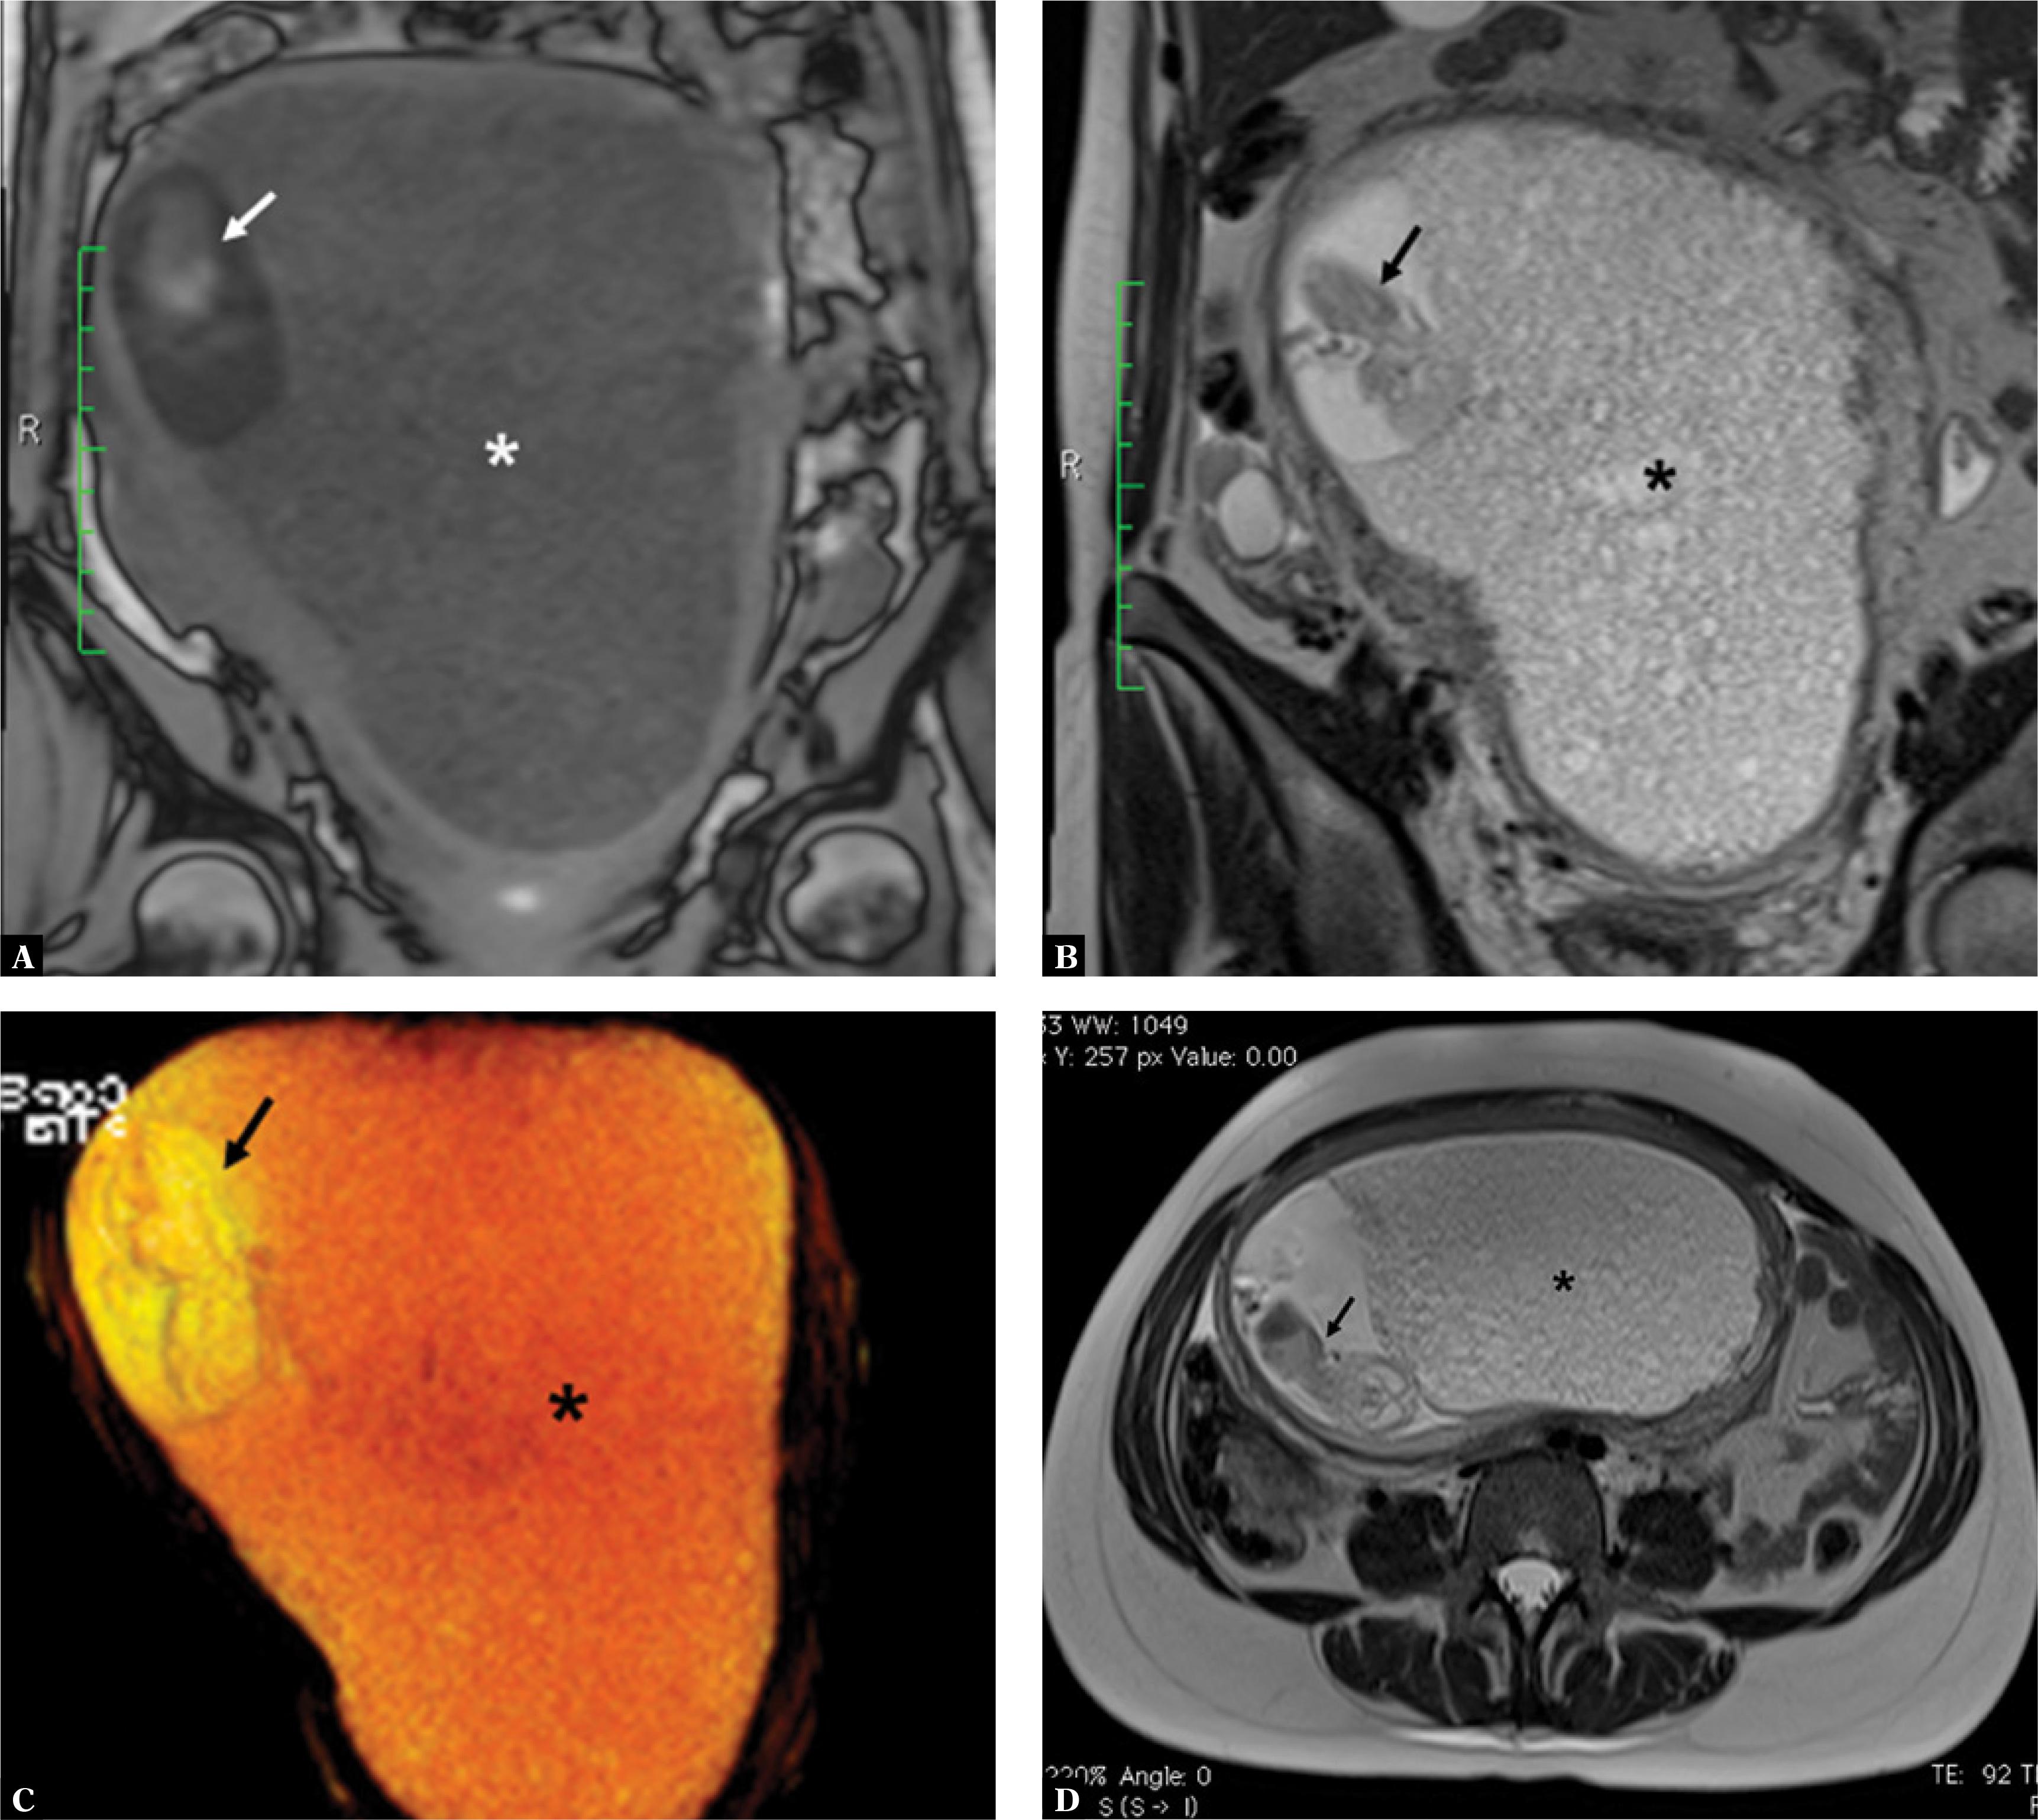

Fig. 3